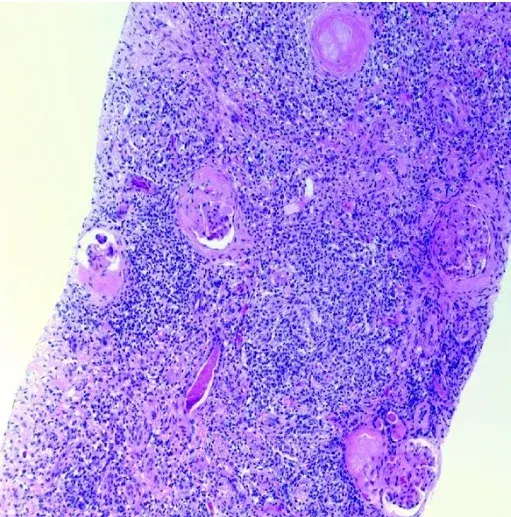

IRA na cirrose, nem sempre é síndrome hepatorrenal!

IRA na cirrose, nem sempre é síndrome hepatorrenal!

Pacientes portadores de cirrose hepática que evoluem com IRA possuem uma complexidade a parte. Confere essa revisão do CJASN.